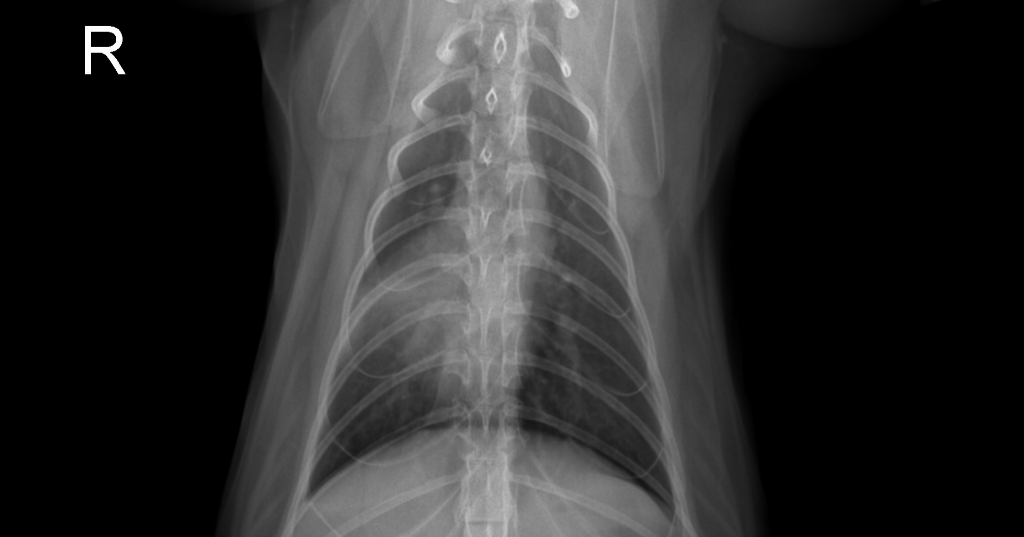

사진한장으로는 진단하지 않는게 원칙이라 정확할 수 없는 쇼견이나

우측 폐 중엽부의 밀도 증가와 함께 심장이 그쪽으로 이동하여 관찰되기에 우측 폐 중엽의 협착과 과거의 폐렴가능성을 의미합니다.

즉, 현재의 증상과는 큰 관련성이 낮으나

만성적인 폐렴이 진행되는 경우, 염증지표가 만성적으로 높거나 골수 억압등의 증상을 보이는경우 수술로 근원인 폐엽을 제거해야합니다.

정기적인 엑스레이 검사를 통해 해당 폐엽의 변화양상 모니터링이 추천됩니다.